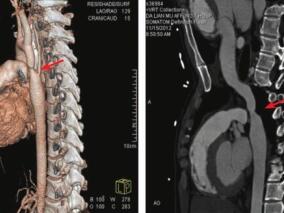

1小时条评论病史摘要 男性,19岁,5年前因受凉后出现咽痛、咳嗽,伴头晕、头痛,于当地诊所测量血压190/110mmHg,遂就诊于大连医科大学附属第一医院儿科,行主动脉CTA示主动脉弓至胸主动脉管腔变细,最小径约9.6mm,诊断为先天性主动脉缩窄,给予降压、对症等保守治疗。出院后...